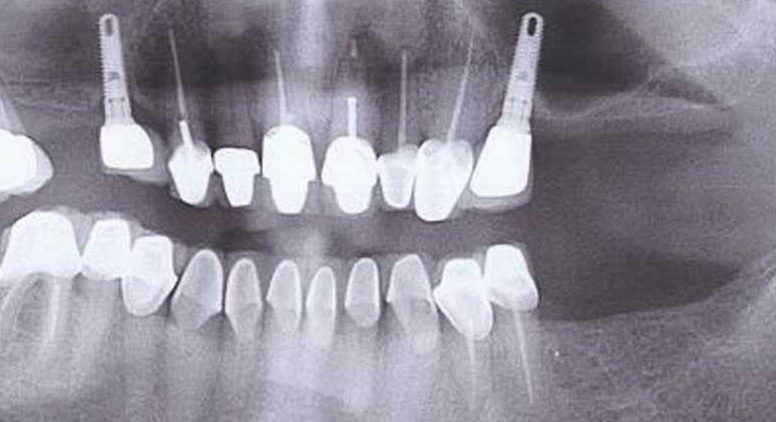

IMPLANTOLOGIE

Implantul Dentar Un implant dentar este un surub de titan care inlocuieste radacina unui dinte care lipseste. Peste acest implant din titan se …